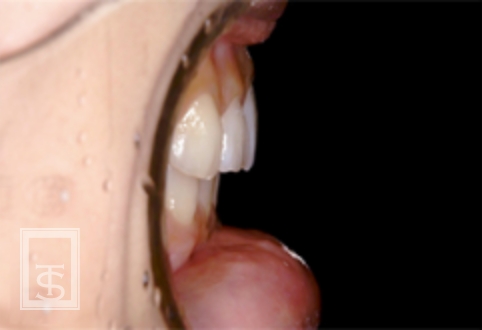

ハーブスト装置(Herbst appliance)

下顎骨成長促進、下顎骨前方誘導を行う装置となります。